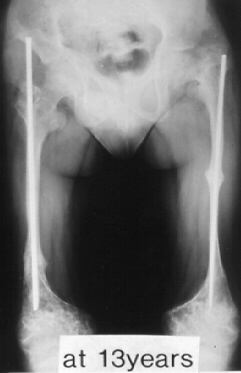

Case 3.

A 14-years-old boy. Body height 124 cm. Sillence type sporadic.

The first visit was at 2 years-old. He sustained one fracture in U/E and 8 fractures in L/E, underwent 10 operations, and has 60 degrees scoliosis. He became able to walk on crutches at 2 years old and had been a practical ambulator until 12 years old. He sustained a fracture at the distal end of right femur where an intramedullaly nail did not reached. He uses a wheelchair for long distant transportation. This case is supposed to be on the border line between ambulator and non-ambulator. The diameter of the femur was 10 mm at 3 years of age and 11mm at 13 years of age. No increase of diameter has been observed despite rather thin intramedullaly nailing.